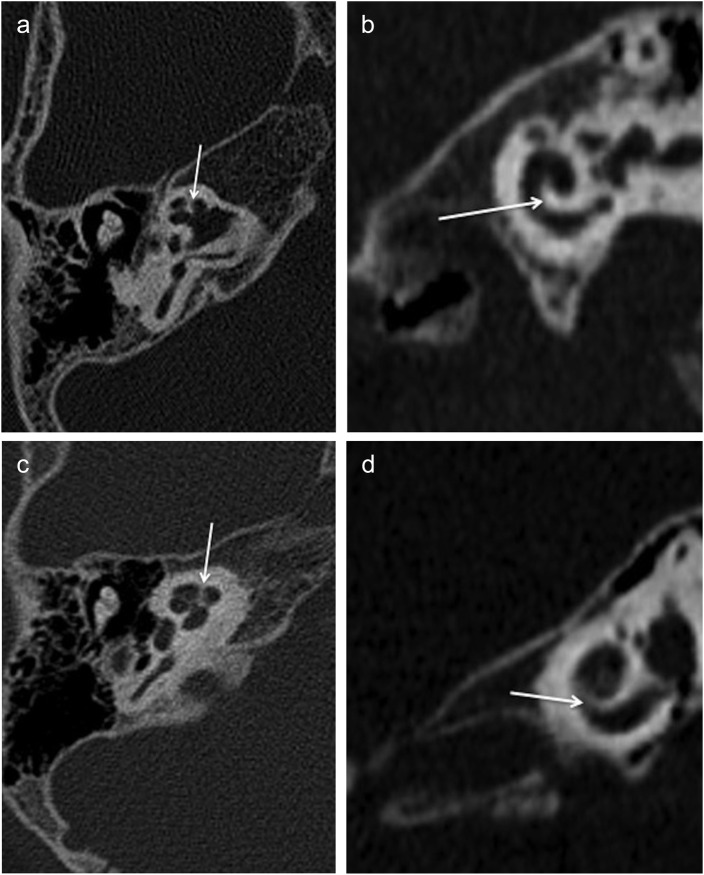

Results: All cases had bilateral IP-III anomaly, bulbous internal auditory canals (IACs), absent bony modiolus with preserved interscalar septa, intact cochleovestibular, and facial nerves. OC thickness was decreased in all cases compared to the control group (p<0.001). In XLD patients, the cochlea had decreased transverse dimension and increased height compared to the control group (p< 0.001). Five patients (38.4%) had bilateral cystic structures adjacent to the vestibule and/or semicircular canals (SCCs). Hypothalamus was thickened or had a lobular appearance in all cases (subtle in one). Additionally, hamartoma-like appearance of the hypothalamus was present in half.

Conclusion: XLD is a rare inner ear anomaly that is frequently associated with hypothalamic malformations. The OC thickness of IP-III patients appears to be decreased with accompanying decreased transverse dimension of the cochlea which could have implications in electrode selection during cochlear implantation. Cystic /diverticular lesions surrounding the vestibule and semicircular canals are also frequently seen but a rarely reported finding.